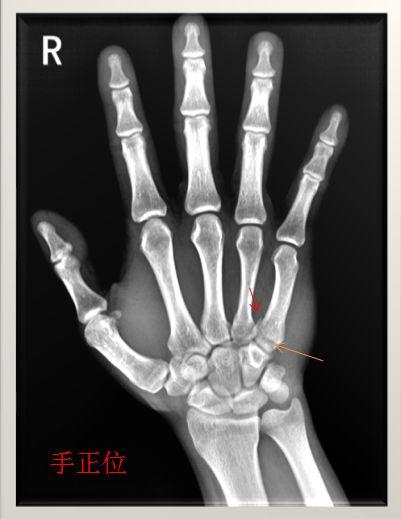

右手第五掌骨骨折

病例2,诊断为右手第五掌骨基底部骨折.

右手第五掌骨骨折(1-5.